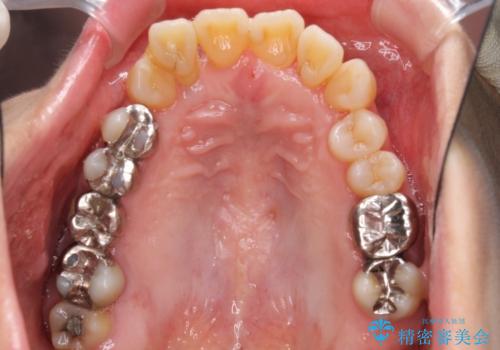

- 歯の欠損や歯肉からの出血などを気にして来院された患者様です。

診査の結果、歯周病であることが分かり、抜歯が必要な歯も見受けられました。

骨造成やインプラント、歯周外科、歯肉移植、矯正など、多くの処置を組み合わせて治療を行うこととしました。